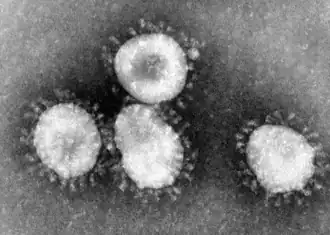

Das schwere akute Atemwegssyndrom, auch Schweres Akutes Respiratorisches Syndrom (englisch severe acute respiratory syndrome, SARS) genannt, ist eine Schwere Akute Atemwegsinfektion (SARI), die erstmals im November 2002 in der südchinesischen Provinz Guangdong beobachtet wurde.[1] Laut dem Bernhard-Nocht-Institut für Tropenmedizin in Hamburg entspricht das klinische Bild einer atypischen Lungenentzündung (Pneumonie). Der Erreger von SARS war ein bis dahin unbekanntes Coronavirus, das man inzwischen als „SARS-Coronavirus“ (SARS-CoV-1) bezeichnet. Die SARS-Pandemie 2002/2003 forderte knapp 800 Todesopfer.[2]

Zunächst wurden Paramyxoviren als Ursache von SARS vermutet. Um den 26. März 2003 erhärtete sich jedoch der Verdacht, dass der Erreger zur Familie Coronaviridae gehört. Er wurde gleichzeitig an der Universität Hongkong, an den Centers for Disease Control and Prevention (CDC) in Atlanta und am Bernhard-Nocht-Institut für Tropenmedizin in Hamburg als neues Coronavirus identifiziert. Anhand der Gensequenzen wurde vermutet, dass ein bekanntes Coronavirus entweder mutiert oder dass eine Virusart, die bisher nur Tiere befallen hat, auf den Menschen „übergesprungen“ war. Weitere Untersuchungen konzentrierten sich daher auf das neu entdeckte Coronavirus und als weitere Faktoren auf Chlamydien und Paramyxoviren. Bisher sei nichts gefunden worden, „was gegen die ursächliche Rolle des Coronavirus spricht“, hieß es aus Fachkreisen. Am 12. April 2003 gab Marco Marra, Direktor des Michael Smith Genome Sciences Centre der British Columbia Cancer Agency, bekannt, es sei ihm gemeinsam mit anderen kanadischen Forschern gelungen, die RNA-Sequenz des Virus zu entschlüsseln. Vier Tage darauf veröffentlichte die WHO eine Pressemitteilung mit der Erklärung, das von mehreren Laboratorien identifizierte Coronavirus sei der offizielle Auslöser von SARS. Es erhielt die wissenschaftliche Bezeichnung „severe acute respiratory syndrome coronavirus“ (SARS-CoV). Zwei Tage nach Identifizierung des Virus gelang es den Virologen Christian Drosten und Stephan Günther vom Bernhard-Nocht-Institut als ersten, einen diagnostischen Test zu entwickeln, der inzwischen weltweit eingesetzt wird.[3] Die Gruppen vom CDC, der Erasmus-Universität in Rotterdam, der University of San Francisco und Bernhard-Nocht-Institut publizierten gemeinsam[4] 2003 in Science über die Entdeckung des SARS-Coronavirus und der Bestimmung von dessen Genomsequenz ebenso wie die kanadische Gruppe um Marco Marra.[5]